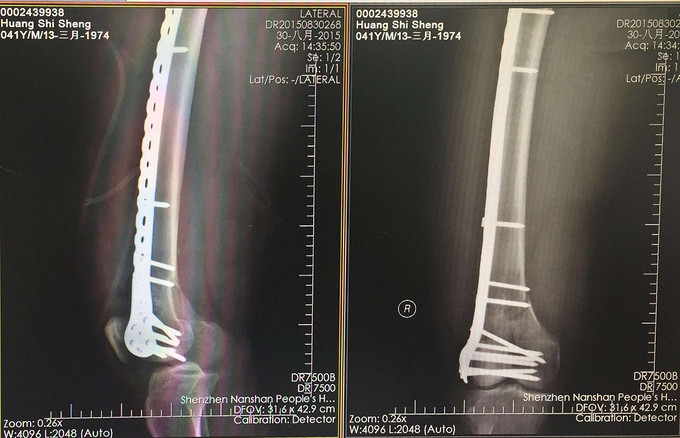

查体:右大腿中下段短缩成角畸形,肿胀,可扪及骨擦感,患肢末梢感觉血运可。 X:右股骨下端骨折 CT:右股骨下端骨折,波及关节面。

右股骨远端粉碎性骨折 完善检查,行右股骨远端骨折切开复位内固定术。